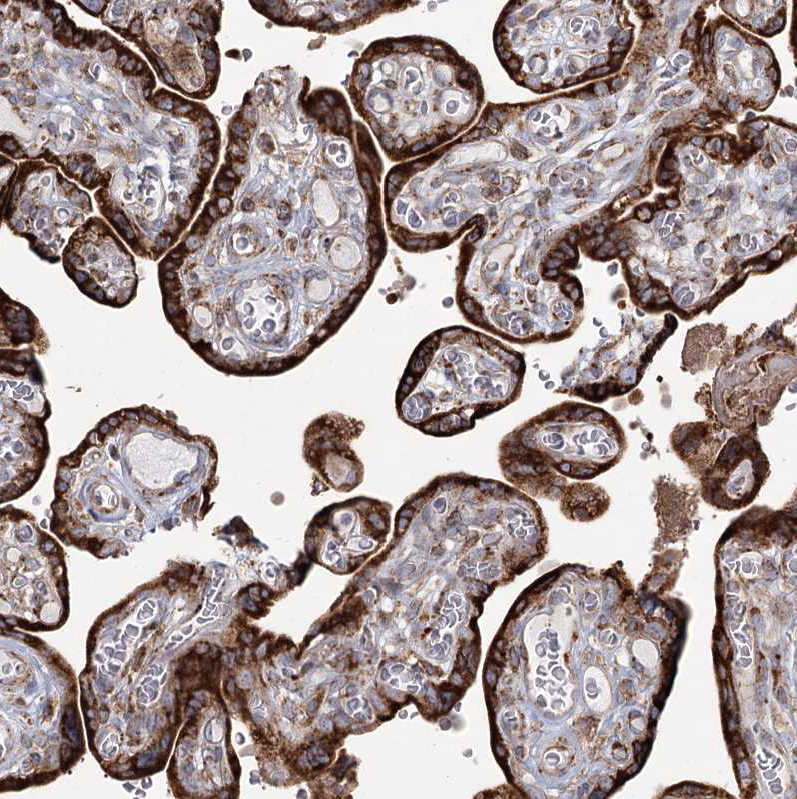

Immunohistochemical staining of human prostate shows strong cytoplasmic positivity in glandular cells.